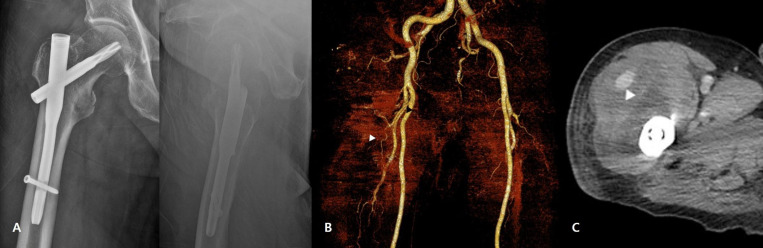

股骨粗隆间骨折引起的血管损伤是罕见的,但可导致严重的并发症。一例医源性损伤的外侧旋股动脉降支的病人接受手术固定股骨粗隆间骨折。损伤可能发生在使用导针插入钉入点的过程中。术后10天出现临床症状,经皮栓塞治疗成功,无重大并发症。本病例强调在髋关节内钉过程中使用导针可导致假性动脉瘤。外科医生可以通过获得髋关节的侧面和正前方视图来避免这种并发症。证据等级:IV,病例报告。

Vascular injuries associated with femoral intertrochanteric fractures are rare but can result in serious complications. A case of iatrogenic injury to the descending branch of the lateral circumflex femoral artery in a patient who underwent surgical fixation of an intertro-chanteric femoral fracture is presented. The injury possibly occurred during the creation of the entry point for nail insertion using a guide pin. Clinical symptoms emerged 10 days postoperatively and were successfully managed with percutaneous embolization, without major complications. This case highlights that pseudoaneurysms can develop as a result of guide pin use during hip nailing procedures. Surgeons can avoid this complication by obtaining lateral and anteroposterior views of the hip. Level of Evidence: IV, Case Report.